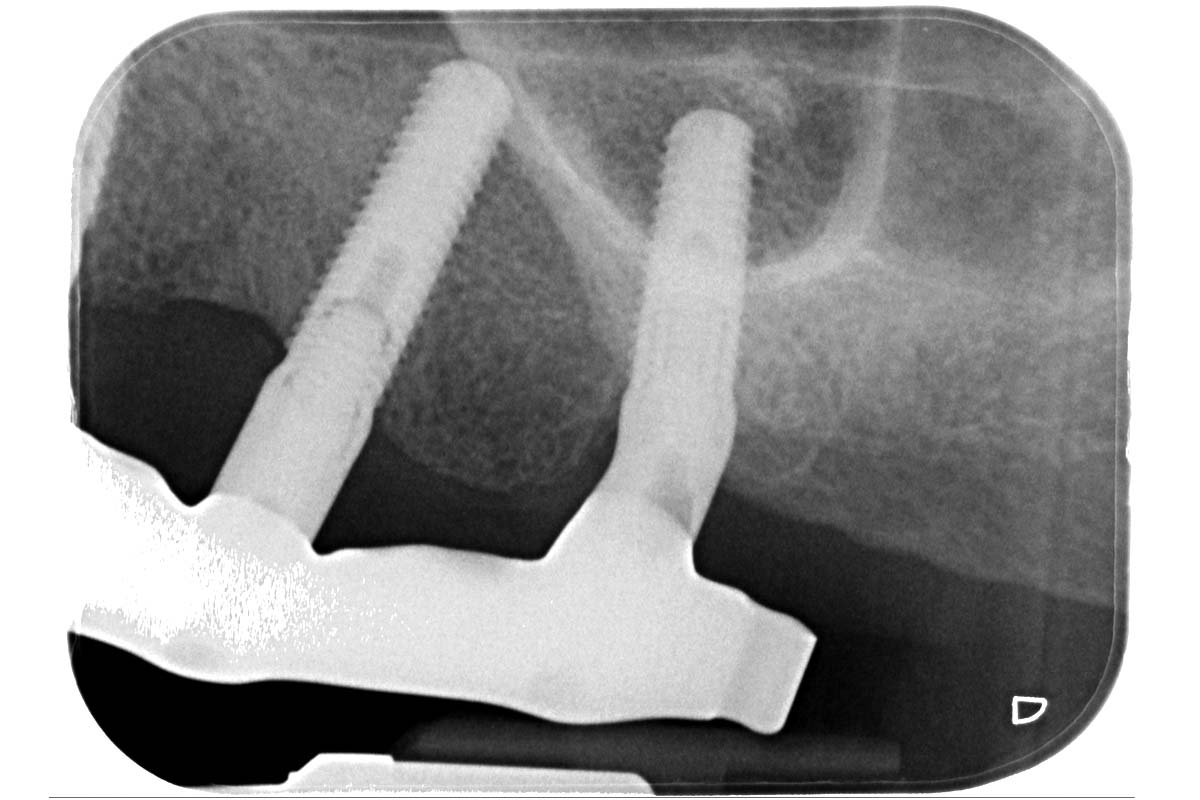

Ridge augmentation with maxgraft® bonebuilder and sinus floor elevation – Dr. K.P. Schiechl

Initial clinical situation: Bone defect in the upper right maxilla (teeth #14-16)